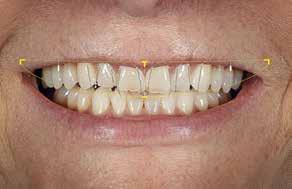

I samråd med patienten og egen tandlæge* afstemmes forventningerne, inden der bestilles refinement alignere. Nivelleringen af alle tænder i tandbuerne, smilelinje og -kurve samt den bukko-lingvale position af incisiverne foretages og efterfølges af retainers lingvalt på over- og underkæbeincisiver (Fig. 3 A-D). Hele behandlingen udføres under løbende kommunikation med patient og egen tandlæge*, der udfører den efterfølgende rekonstruktion med direkte plast (Fig. 4 A-D). Behandlingsvarigheden har været to år og to måneder, hvor ortodontien har forløbet over 21 måneder. Der har været anvendt et første sæt på 66 alignere samt yderligere to sæt med ni refinement alignere. Tandblegning og direkte plastrekonstruktion er udført af egen tandlæge* (Fig. 5 A-F).

Fig. 5. A, B. Smil og kæbeforhold før og efter. Et bredere smil med korrektion af de laterale mørke rum. C-F. Harmonisk hældning af overkæbe- og underkæbeincisiver, rekonstruktion af den tabte tandsubstans efter nivellering af gingivaniveau og optimal bukko-lingval placering til direkte plastbehandling.

5. A, B. Smile and jaw relationships before and after. A wider smile with correction of the lateral dark spaces. C-F. Harmonious inclination of the upper and lower jaw incisors, reconstruction of the lost tooth substance after leveling the gingival level, and optimal bucco-lingual positioning for direct plastic treatment.